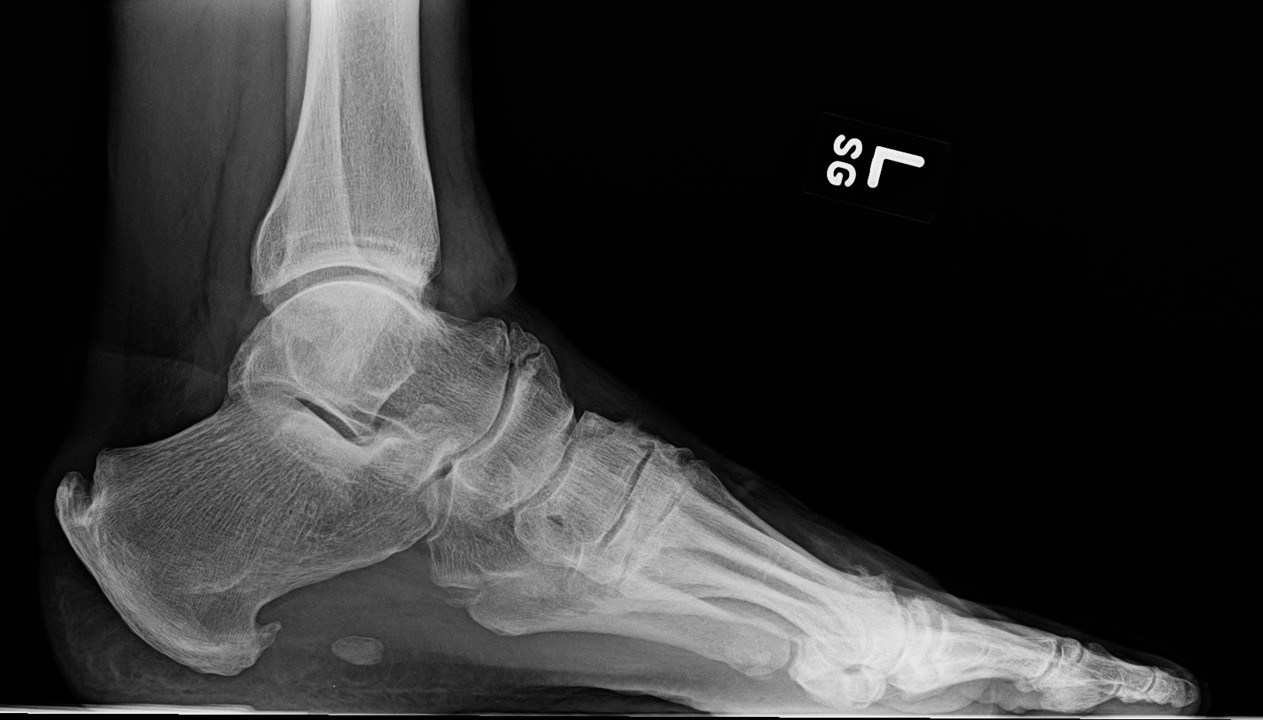

FIGURES 1: Midfoot osteophytes and joint space narrowing in left foot of 56-year-old male. (Click to enlarge.)

Midfoot osteoarthritis (OA) is a subtype of foot OA in which OA exists in one or more joints of the midfoot, most often the tarsometatarsal, talonavicular or naviculocuneiform joints (see Figure 1). OA in this region is relatively under-recognized but is a key contributor to foot pain and disability, especially in middle-to-older-aged adults.